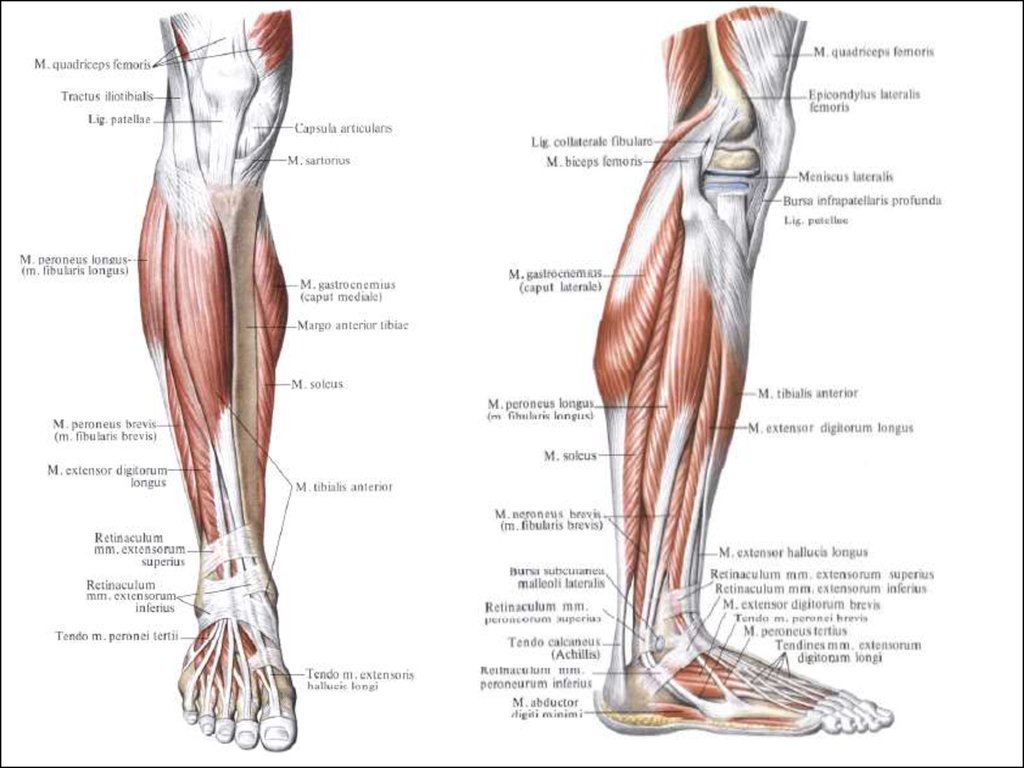

Анатомия подошвенной мышцы голени: подробное рассмотрение